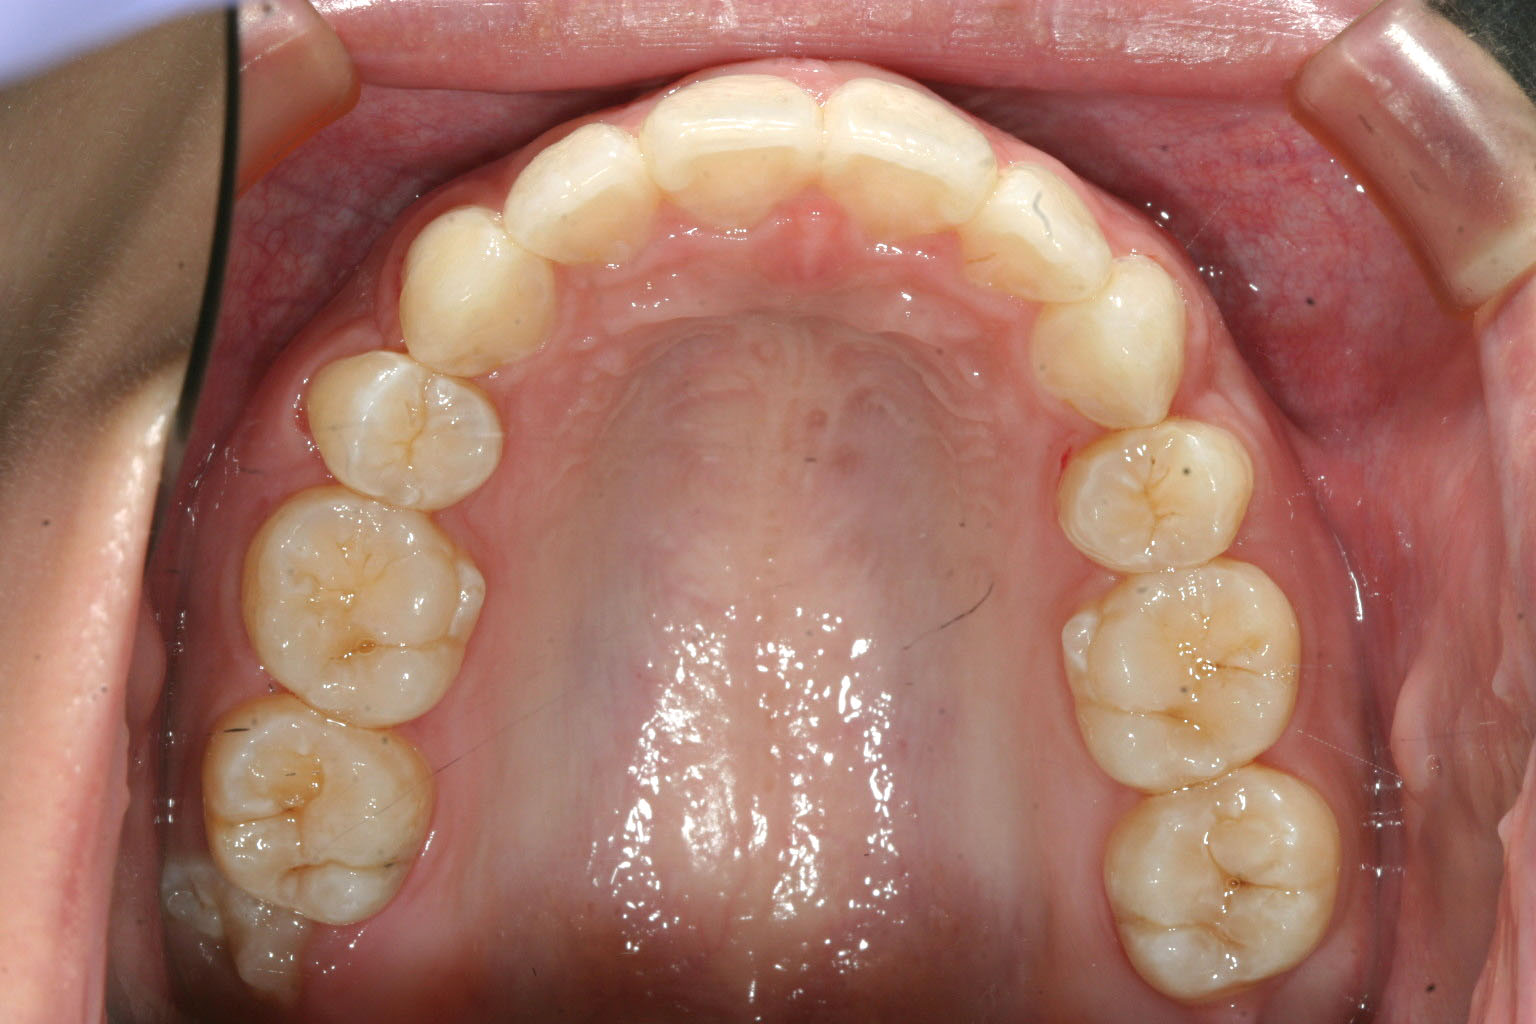

上の写真と見比べてください、かなり引っ込みました。

今回の症例は過度の上顎前突の上顎小臼歯抜歯による矯正症例です。

こちらの症例は上顎が下顎に比べて全体的に前方に移動していた為、やむなく上顎の左右小臼歯抜歯を行いました。

一般的に小臼歯抜歯を行う矯正治療には3年前後の治療期間を要するとされていますが、今回は加速矯正装置を使用する事で半分以下のの治療期間で終了する事が出来ました。

インビザラインの様なマウスピース矯正装置と加速矯正装置は相性が良く期間を大幅に短縮する事が出来ます。